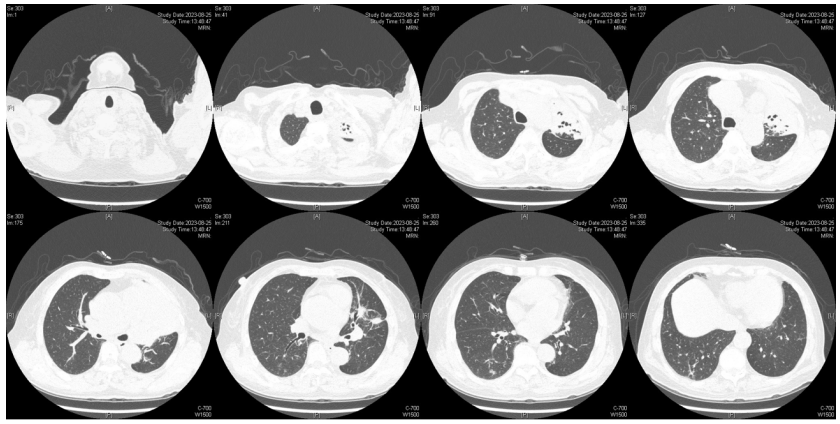

由于厌氧菌培养非常困难,既往我们对厌氧菌的认知仅限于在消化道定植,对其致病机制以及何种情况下致病并不非常清楚。厌氧菌定植于皮肤黏膜,是一种内源性微生物,感染发生率高,可导致严重、致死性感染。由于标本采集和转运的特殊性,使厌氧菌难以分离;加之其培养困难,体外生长慢,所以既往很难识别。厌氧菌在治疗方面存在一定挑战,如往往混合多重感染,且易产生耐药,也会因治疗延迟导致治疗失败。随着近10年来NGS技术的应用和普及,我们对厌氧菌的认识得以提升。常见的致病厌氧菌分为革兰阳性球菌、革兰阴性球菌、革兰阳性非芽孢杆菌、革兰阳性芽孢杆菌以及革兰阴性杆菌(表1)。革兰阳性非芽孢杆菌中可能致病的是放线菌,例如龋齿放线菌参与龋齿的发病过程。革兰阳性芽孢杆菌往往具有致病性,其中产气荚膜杆菌、艰难梭菌/难辨梭状芽孢杆菌、肉毒杆菌/肉毒梭菌、破伤风梭菌/杆菌具有强致病性。革兰阴性杆菌中的拟杆菌属对青霉素类药物具有很强的耐药性,易致青霉素治疗失败。临床中我们与厌氧菌的接触逐渐增多,对其特点也会愈发熟悉,对于临床诊断和治疗也会有所帮助。在NGS报告中通常会将检出的厌氧菌列为“C类”,定义为致病性C类—呼吸道正常微生态菌群,一般不导致感染。但当患者存在误吸风险时,需关注厌氧菌引起肺脓肿的可能。此时就需要针对患者的危险因素、临床表现、影像学、病原学以及气管镜下特点等进行综合分析。微小单胞菌最早是通过培养进行鉴定。瑞士2015—2022年132例病例报告的培养鉴定结果显示,血液中检出微小单胞菌37例(28%),肺内(肺脓肿、脓胸)检出29例(22%),总体病死率较低(5.3%)。国内周华教授团队开展的一项回顾性研究分析了2019年1月至2020年7月经病理活检和mNGS诊断的5例与微小单胞菌相关的慢性肺脓肿患者。患者的平均病程为6.5个月,共同特征是口腔卫生差,有酗酒史,且CT表现为边界不规则的高密度团块状实变影,并且在病灶中间可见液化性坏死,但没有发现气液平面或空腔,所以前期易被误诊为肺癌。下图1是该研究报告中病例3的肺部CT表现。时间点1:首次就诊时,左下叶可见团块状肺不张,伴周围磨玻璃样渗出病变,中心坏死不明显,可见细小空气囊泡影。时间点2:发病8个月时,可见大面积肺实变,增强CT示病灶内有液化坏死和小空洞。时间点3:经过3个月的有效抗厌氧菌治疗,病灶明显缩小,遗留空洞和纤维增殖病灶。图2是病例4的肺部CT表现。时间点1:患者首次就诊时,右上叶可见肿块样肺部实变影。时间点2:发病8个月时增强CT,可见实变明显增大,病灶内出现液化坏死。时间点3:经过3个月的有效治疗,病灶明显缩小,有残留空洞和纤维瘢痕样病变。由于通过影像学鉴别该病与肺癌具有挑战性,所以5例患者都接受了支气管镜检查和CT引导下经皮肺活检。5例患者经组织活检或支气管肺泡灌洗液(BALF)标本mNGS检测到微小单胞菌。病例: 女性, 67岁, 主诉"咳嗽咳痰2个月"。现病史:2个月前,患者家属感染新冠病毒(家属新冠抗原阳性)之后,患者出现咳嗽咳黄脓痰,无痰中带血及痰液拉丝,痰无臭味,无胸闷气短及胸痛,无咽痛咽痒,无鼻塞流涕。6月9日于当地市医院住院,住院期间出现发热,体温最高38.6℃,无寒战,查新冠病毒核酸阳性,予先诺特韦/利托那韦片口服治疗。查胸部CT见左肺上叶软组织影,左肺上叶炎症。诊断肺脓肿,予头孢唑肟联合莫西沙星,治疗后复查胸部CT(6月26日)病灶较6月9日明显吸收好转。6月14日气管镜检査见左肺上叶支气管开口狭窄,见大量脓性痰液堵塞支气管开口(病原学结果家属无法提供)。6月30日办理出院后仍有咳黄脓痰,无发热畏寒,口服止咳化痰药物,未使用抗生素。7月30日复诊胸部CT见左肺上叶异常密度较前增大。8月2日再次于当地市人民医院住院。8月4日气管镜检查: 左肺上叶黏膜肿胀肥厚, 管腔狭窄, 见大量白色干酪样分泌物涌出, 支气管镜不能进入。内科予莫西沙星静滴治疗10天, 外科予莫西沙星联合哌拉西林他唑巴坦静滴9天。复查胸部CT见病灶较前进展, 且右肺出现新发感染病灶。病程中患者饮食可, 睡眠差, 二便正常, 体重减轻5 kg。既往对阿莫西林过敏, 表现为口服阿莫西林后全身皮疹。否认嗜酒史及吸烟史。入院后胸部增强CT可见病灶内液化坏死,同时伴有小的空气囊泡影(图3)。患者有胸痛症状。气管镜检查发现气道内有痰栓或黏液栓阻塞征象(图4)。灌洗液tNGS结果回示:微小单胞菌(序列数2762),巨细胞病毒(序列数171),副流感病毒(序列数79),EB病毒(序列数61)。考虑病毒不会导致气道内如此改变,但由于微小单胞菌属于常见口腔定植菌,此时也不能完全确定微小单胞菌是否为引起感染的主要责任病原体。8月24日起予莫西沙星0.4 g qd ivgtt+哌拉西林他唑巴坦4.5 g q8h ivgtt。经过上述治疗,患者局部病灶有所吸收,但整个肺叶并无明显改善(图5)。气管镜检查仍然发现气道内有较黏稠的黏液栓阻塞气道开口(图6)。治疗经过:气管镜下予以局部冲洗,再次送检tNGS。9月7日结果回示:微小单胞菌(序列数6464),较前明显增多;副流感病毒(序列数998),EB病毒(序列数331)。9月9日起调整治疗方案为美罗培南1 g q8h。9月12日复查患者胸部CT,可见肺通气部分改善,肺组织内实变较前吸收(图7)。第三次气管镜检查仍可见少量痰栓嵌塞在远端支气管开口(图8)。患者此后转入医联体医院继续抗感染治疗。病例2:女性,54岁。主诉:咳嗽咳痰2个月,发热1周。现病史:入院2个月前,患者在西南地区旅游时感冒,出现咳嗽咳痰,白痰为主,量多,无胸痛,无发热,无痰中带血,咳时气短。于河北某诊所间断输液治疗14天(具体不详),期间口服中药治疗,症状未缓解。入院3周前(2023-09-07)就诊于当地县医院,查胸部CT提示右肺炎症,静脉滴注氨曲南、左氧氟沙星、氨溴索治疗1周,症状未缓解。2023年9月14日复查胸部CT显示右肺炎症较前加重,于当地中心医院住院。动脉血气分析:pH 7.43,PaCO2 38.4 mmHg,PaO2 67 mmHg,SaO2 94.2%;血沉90 mm/h;生化:白蛋白35.3 g/L;CRP 82.7 mg/L;血常规:WBC 9.75×109/L,NEU 6.83×109/L,HGB 104 g/L。静脉滴注莫西沙星。入院10天前,行肺穿刺活检,病理回报为少量肺组织及纤维结缔组织,炭末沉积,较多中性白粒细胞、淋巴细胞及浆细胞浸润,伴脓肿形成;肺穿刺mNGS结果回报:微小单孢菌(序列数2650),鲍曼不动杆菌(序列数17),人类疱疹病毒4型(序列数60),人类疱疹病毒7型(序列数5),文氏密螺旋体(序列数4337),解卵磷脂密螺旋体(序列数1121),齿垢密螺旋体(序列数698)。调整抗生素为头孢哌酮舒巴坦2 g q12h。入院1周前,出现发热,体温最高38.5℃,不伴寒战,咳嗽咳痰无加重,无咯血;复查血常规、PCT、CRP均明显增高(未见报告单);复查胸部X线提示右肺炎症范围增大,右侧胸腔积液。更换抗生素为哌拉西林他唑巴坦4.5 g q8h。4天前,支气管镜下见右肺下叶背段支气管略狭窄,黏膜水肿,可见脓性分泌物溢出。BALF革兰染色查见革兰阴性杆菌,抗酸染色、霉菌未见异常,培养未回报。患者体温逐渐降至正常,咳嗽咳痰有所减轻,复查胸部CT提示右肺高密度影,右侧胸腔积液较前增多。为求进一步诊治来我院就诊被收入院。既往甲状腺功能减退病史5年,目前口服优甲乐治疗,监测甲状腺功能指标在正常范围。20年前因宫外孕行手术治疗。2023年10月8日胸部CT示胸膜下斑片状坏死,纵隔窗可见微小空气囊泡影及密度不均匀液化坏死(图9)。治疗:9月28日至10月13日莫西沙星0.4 g qd ivgtt+哌拉西林他唑巴坦钠4.5 g q8h ivgtt。最终患者病灶吸收好转并顺利出院。患者男性,42岁。主因间断咳嗽、咳痰1月余,左侧胸痛、气短2天入院。现病史:入院前1月余(2022-07-19),患者无明显诱因出现咳嗽,咳白痰,痰中有少量鲜红色血丝,左侧胸痛(为钝痛),深吸气后加重,就诊于当地医院。完善肺动脉CTPA:示左上肺动脉舌段分支局部管腔可见线条样低密度充盈缺损,考虑肺栓塞;左肺上叶实性病变伴不均匀强化,性质待定,部分为肺梗死改变可能,纵隔多发稍大淋巴结,性质待定;右肺下叶后基底段可见一不规则实性结节,边缘可见多发毛刺,直径约0.7 cm。当地医院考虑肺栓塞不除外,肺部感染?右肺下叶结节,予莫西沙星抗感染,低分子肝素抗凝,乙酰半胱氨酸化痰。完善CT引导下肺穿刺活检,病理示:肺泡腔扩张伴上皮轻度增生,肺泡间隔纤维组织增生伴散在炎细胞浸润,未见恶性病变。院外规律应用甲磺酸艾多沙班60 mg bid抗凝,先后间断应用左氧氟沙星0.5 g qd、头孢类抗生素(具体药物、剂量不详)抗感染。患者仍有间渐咳黄白痰,量不多,痰中有少量鲜红色血丝;无畏寒、发热、胸痛、夜间阵发性呼吸困难症状,无尿少、双下肢水肿,无口干、咽干,无牙齿成片脱落,无晨僵、关节肿痛,周身无皮疹,无盗汗乏力。2天前(2022-09-16)患者无明显诱因再次出现左侧胸痛,疼痛剧烈,深吸气、咳嗽及改变体位时加重,伴气短,就诊于我院急诊。完善肺动脉CTPA:肺动脉主干及其各叶段分支未见明显充盈缺损,左肺上叶舌段团块影,最大截面约7.6 cm×5.3 cm,边界不清,周围可见晕征;增强扫描不均匀强化,邻近胸膜增厚,性质待定,建议穿刺活检;纵隔及左肺门多发淋巴结显影。血细胞分析:WBC 11.09×109/L,NEU% 80.8%,NEU 8.95×109/L;CRP 54 mg/L,PCT 0.07 ng/ml。患者自发病以来,精神状、食欲及睡眠均一般,大小便正常,体重下降5 kg。2022年9月14日外院胸部增强CT:胸膜下楔形的影像学表现可见少量小气泡囊以及液化坏死病灶(图10)。初始考虑肺部肿瘤及肺栓塞。经过初步抗感染及抗凝治疗,患者病情无缓解,2022年9月27日患者突发胸痛,下肺影像加重并且出现脓胸(图11)。行胸腔穿刺并将脓液送检mNGS,结果回报:牙龈卟啉单胞菌(序列数3)。尽管序列数很低,但考虑是脓肿穿刺结果,因此考虑该菌致病可能。抗厌氧菌治疗:9月16-28日莫西沙星0.4 g qd ivgtt,9月23日-10月12日美罗培南1 g q12h ivgtt,9月28日-10月8日万古霉素1 g q12h ivgtt,10月13-18日莫西沙星0.4 g qd ivgtt+甲硝唑0.5 g tid ivgtt。患者肺脓肿的整体治疗时间约为3个月,病灶逐渐吸收,最终形成一些纤维索条影(图12,图13)。1年后复查病灶基本吸收(图14)。图14 1年后复查胸部CT(2023-08-08)微小单胞菌和卟啉单胞菌这两种厌氧菌在临床中需要引起重视,它们容易引起肺脓肿/脓胸。2024年国内学者Li Yao等在Diagn Microbiol Infect Dis 杂志发表了一篇牙髓卟啉单胞菌感染所致肺脓肿的病例报告,文章也提到在胸水或肺组织活检中,通过mNGS同时检出了微小单胞菌和卟啉单胞菌感染引起的肺脓肿。文章还回顾总结了既往发表的厌氧菌感染引起肺脓肿的病例,2010年报道的是1例脑脓肿患者,2019年报道1例脑炎患者,2022年报道1例脓胸伴呼吸衰竭患者。3例患者预后都比较好,可见厌氧菌亦可导致肺外多部位感染。对于厌氧菌所致肺脓肿的诊断及其引起的脓胸,目前的文献报道仍然较少,我们对它们的认知也有限,因此也提醒大家关注相关疾病的诊断和治疗。我们也已将本研究小组8例微小单胞菌所致肺脓肿的系列病例的研究结果发表(Front Cell Infect Microbiol, 2024, 14: 1416884),可供需要的同行参考。对于厌氧菌感染,我们需要提高警惕。厌氧菌往往在口咽部定植,其引起的脓肿/感染往往多为亚急性或慢性起病。患者通常有发热、胸痛症状,脓肿会逐渐进展。由于厌氧菌与人体本身是一种长期共生的关系,人体对厌氧菌的免疫识别可能处于较低的防御反应状态,所以会形成一个亚急性或慢性的发病过程。通常情况下,因厌氧菌的菌群发生了移位,从卫生条件不好的口腔扩展到相对无菌的肺内,同时开始增殖,由此可能导致感染。因此,对于酗酒以及口腔卫生非常差的人群,我们要重视对其风险因素和病史的排查。患者就诊时可能病情并不重,有胸痛或咯血,很容易误诊为肺部肿瘤,往往在这种情况下进行肺穿刺或气管镜检查,mNGS可以发现较大序列数的厌氧菌。但在mNGS检出厌氧菌后的诊断过程中又容易形成误判——究竟是致病菌,还是定植菌?此时结合患者其他病史和影像学特点(有脓肿/痰栓形成,微小空气气囊泡影),可能提示厌氧菌感染。然而,厌氧菌感染在病原学和影像学诊断方面仍然存在诸多困难,极易漏诊和误诊。微小单胞菌感染患者在气管镜下可以看到典型的脓性分泌物嵌塞气道,导致气道阻塞,也会造成远端气道和肺泡引流障碍。所以,及时处理气道内痰栓,改善引流,可能是使患者获得良好预后的关键。厌氧菌肺脓肿的吸收比较缓慢,抗感染的疗程也比较长,需要在后期诊疗过程中密切随访和观察患者对治疗的反应以及耐药等问题,及时调整治疗方案,适当延长疗程。